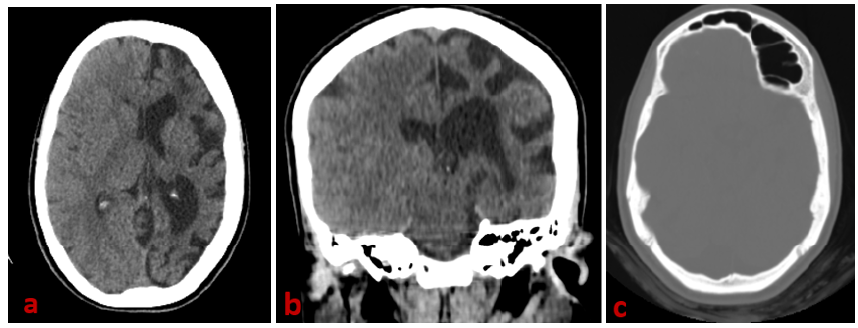

Adult Presentation of Dyke Davidoff Masson Syndrome

El Mansoury Fatima Zahrae, Chalh Olaya, Lahkim Mohammed, En-Nafaa Issam and El Fenni Jamal. 6(3): 01-04.